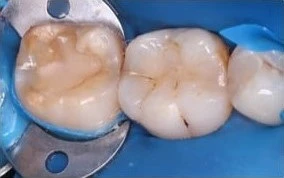

- Для реставрации жевательной поверхности зуба предпочтительным будет применение вкладки;

Для реставрации дефективных участков зубов применяются микропротезы, размер которых определяется степенью разрушения единиц. Ортопедические конструкции изготавливают из различных материалов. Среди них: керамика, пластик, композитные материалы, металл.

Процедура микропротезирования включает следующие этапы: